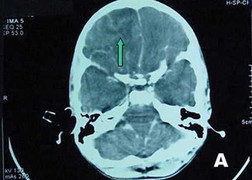

Người đàn ông tên Wang đến từ Trung Quốc bị nhiễm ký sinh trùng (sán dây) do thường xuyên ăn ốc trong các bữa tối.